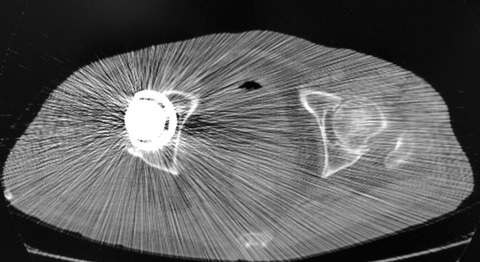

かなり自分に都合の良い希望的バイアスが入っていますね(笑)。では、実際には何度ぐらいなのでしょう。下図は術後CT(臥位)です。臥位なので、カップの前方開角は0度です。

カップの前方開角と寛骨臼の前方開角は、全く合っていないことが分かります。寛骨臼の前方被覆がほとんどありません。解剖学的な寛骨臼の形態に対して反抗的なカップ設置角度です。